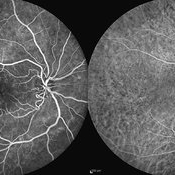

Behcet's Disease Behcet's DiseaseMar 13 2013 by Hamid Ahmadieh, MD Early phase FA of the right eye of a 23-year-old man with retinal vasculitis and branch retinal vein occlusion (BRVO) due to Behcet's disease . Photographer: Solmaz Shahmohammad, Negah Eye Center, Tehran Imaging device: Heidelberg Spectralis Condition/keywords: branch retinal vein occlusion (BRVO), retinal vasculitis

Behcet's Disease Behcet's DiseaseMar 13 2013 by Hamid Ahmadieh, MD Mid phase FA of the right eye of a 23-year-old man with retinal vasculitis and branch retinal vein occlusion (BRVO) due to Behcet's disease . Photographer: Solmaz Shahmohammad, Negah Eye Center, Tehran Imaging device: Heidelberg Spectralis Condition/keywords: branch retinal vein occlusion (BRVO), retinal vasculitis